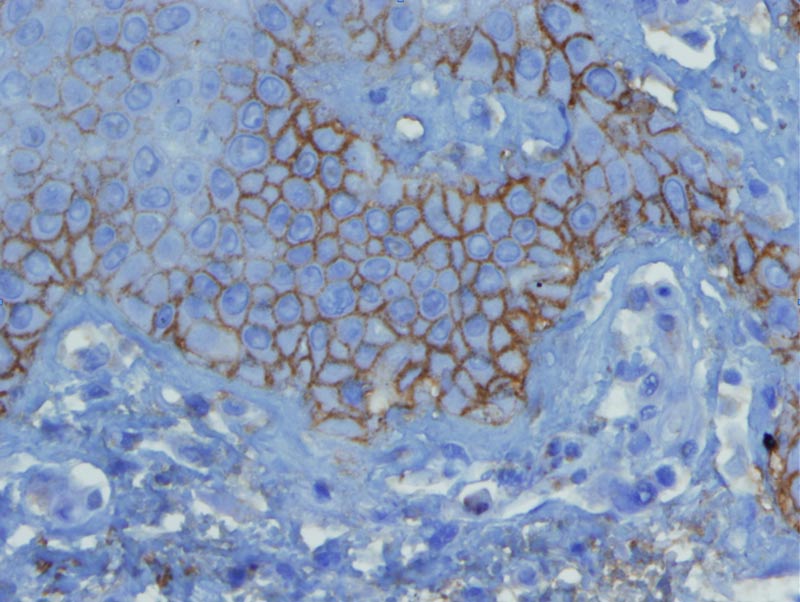

Galéria

db106